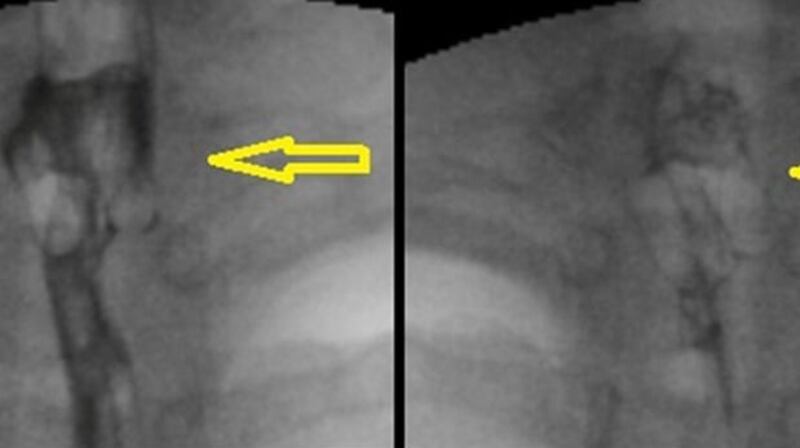

A chest and neck X-ray did not show the pill packet, but revealed an abrasion in her throat – probably caused by her swallowing the packet – which was presumed to be the cause of her discomfort.

Another X-ray was carried out at a hospital five days later, but returned normal results.

The pill packet was finally detected during an outpatient appointment using an oesophagogastroduodenoscopy scan, which examines the upper intestinal tract using a lighted tube.